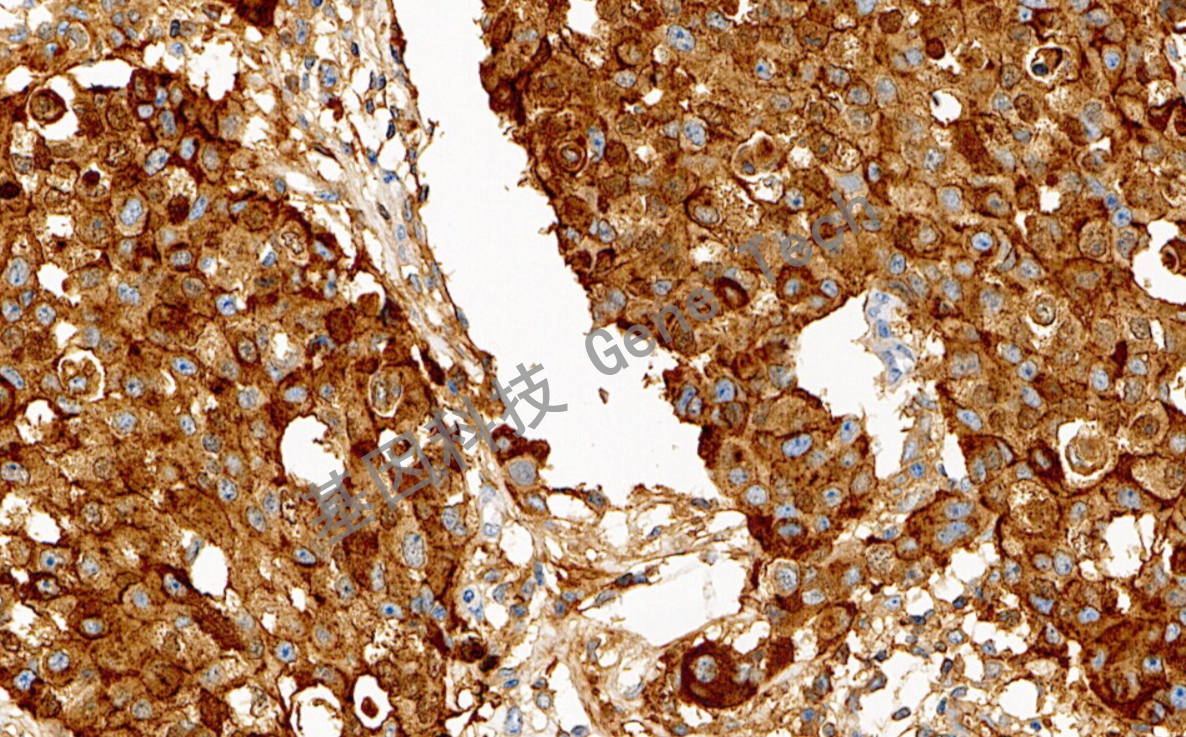

乳腺癌石蜡切片,用 GCDFP-15(GT2049)染色,细胞浆阳性,DAB 显色。

GCDFP-15是一种分子量为15kDa的单链蛋白,常见于囊泡病的囊泡液中。研究发现,GCDFP-15是一种高度特异和敏感的乳腺癌标记物,可用于乳腺癌的鉴别诊断。与CK7和CK20联合使用,用于鉴别原发或继发性乳腺外佩吉特病。